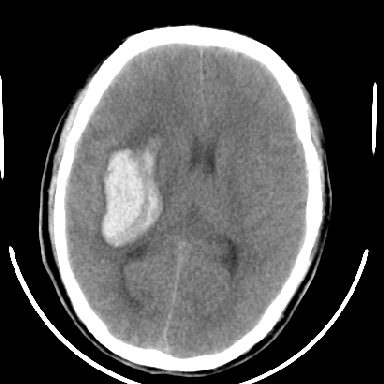

标题: CT6056:脑出血(血管畸形?) [打印本页]

标题: CT6056:脑出血(血管畸形?)

m 40突发头痛左侧偏瘫3小时

考虑高血压性脑出血,依据:

1是高血压性脑出血的好发部位,形态呈肾形,是高血压性脑出血的常见形状

另附部分资料:“血液溢出血管外形成血肿,其内含有大量血红蛋白、血浆白蛋白,球蛋白,因这些蛋白对x线的吸收系数高于脑质,故ct呈现高密度阴影,ct值达40~90h,最初高密度灶呈非均匀一致性,中心密度更高,新鲜出血灶边缘不清。基底节区血肿多为“肾”型,内侧凹陷,外侧膨隆,因外侧裂阻力较小,故向外凸,其它部位血肿多呈尖圆形或不规则形”

术中抽出40ml陈旧血液,血肿底部似见一条索血管影